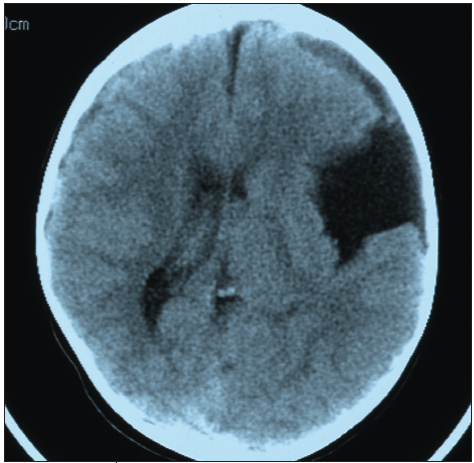

The parents of a 7-year-old girl, who had fallen off her bicycle and hit her left forehead 2 weeks earlier, brought their daughter to the emergency department after she began having increasingly severe...

04/29/2011

Ellen Bass, MD, MPH; Domenick Roma; Dante Pappano, MD, MPH; Alexander K.C. Leung, MD, MBBS, FRCPC, FRCP